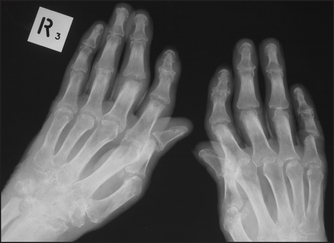

It is not usually necessary to X-ray all symptomatic joints; information about joint destruction and typical changes that help make the diagnosis can be obtained from selected X-rays. For example, a clinical presentation with a polyarthritis may warrant hand and foot X-rays which, if they show erosion and a typical pattern (e.g. metatarsophalangeal and metacarpophalangeal involvement), can help make the diagnosis of rheumatoid arthritis (see Figures 26.6 and 26.7).

Figure 26.7 Rheumatoid arthritis, late findings X-ray of the hands of a patient with advanced rheumatoid arthritis. Note loss of joint space and destruction of the right carpal joints, subluxation of metacarpophalangeal and proximal interphalangeal (PIP) joints, and Z deformity of the thumb. There are erosions of the PIP joints, a sign of active disease.